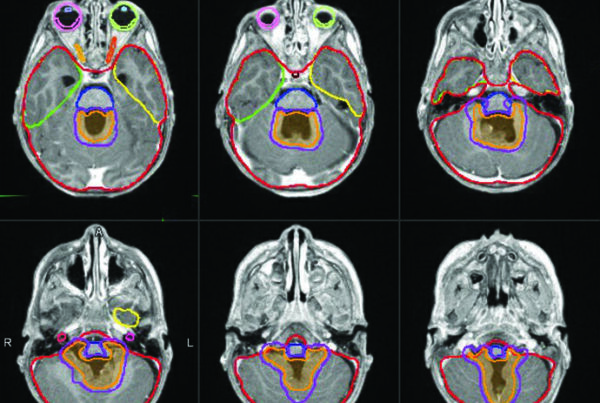

O estudo randomizado citado no capítulo, que comparou irradiação padrão da bexiga inteira com reduced high-dose volume radiation therapy (RHDVRT), não mostrou redução significativa de toxicidade tardia e demonstrou não inferioridade de controle locorregional com o RHDVRT em relação à irradiação da bexiga inteira. Esse resultado mantém duas estratégias abertas para quem trabalha com redução de volume: um boost sequencial em duas fases ou um boost concomitante em fase única. As figuras 26.1 e 26.2 do capítulo ajudam a visualizar essa lógica ao mostrar, respectivamente, as DRRs do campo pélvico pequeno e os esquemas de cone down e SIB.

As figuras 26.3 a 26.5 reforçam como essa estratégia aparece no tratamento real. O capítulo mostra um campo pélvico inicial com IMRT, depois o boost vesical sequencial, e finalmente um exemplo de quimiorradioterapia concomitante com IMRT limitada à bexiga. O valor dessas vinhetas clínicas está em mostrar que a escolha entre pelve completa e bexiga isolada não é abstrata; ela muda o contorno, o PTV e a relação com reto, próstata e alças intestinais.